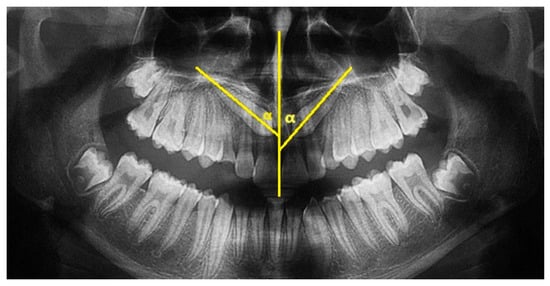

The Lindauer [2] sector division was considered to evaluate the mesio-distal position of canines’ cusps. The authors described four sectors, listed in order of severity of prognosis:

Sector I: area distal to the line tangent to the distal surface of the lateral incisor;

Sector II: area mesial to sector I, distal to the line that divides the mesiodistal surface of the lateral incisor along its major axis;

Sector III: area mesial to sector II, distal to the line tangent to the mesial surface of the lateral incisor;

Sector IV: includes the area mesial to Sector III (Figure 2).

Figure 2.

Sector of inclusion measured on OPT according to Lindauer. Both maxillary canines are included in sector IV.